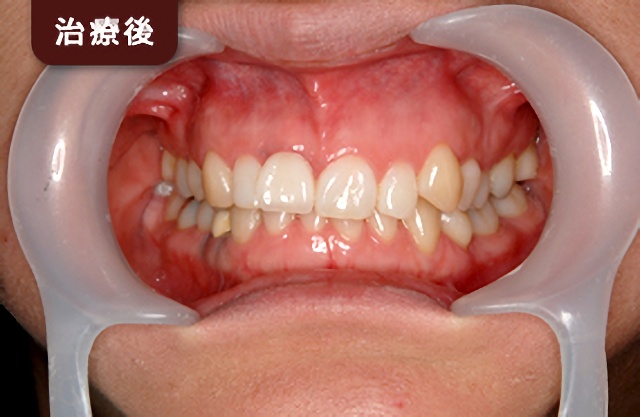

| 総入れ歯 | インプラント |

|---|---|

![]() | ![]() |

| 入れ歯が口の中で動いてしまい、「噛みづらい」や「話しづらい」などの不便さを感じることがあります。 | インプラントにより、入れ歯をしっかりと固定できるので、入れ歯を気にせず食事や会話を楽しむことができます。 |